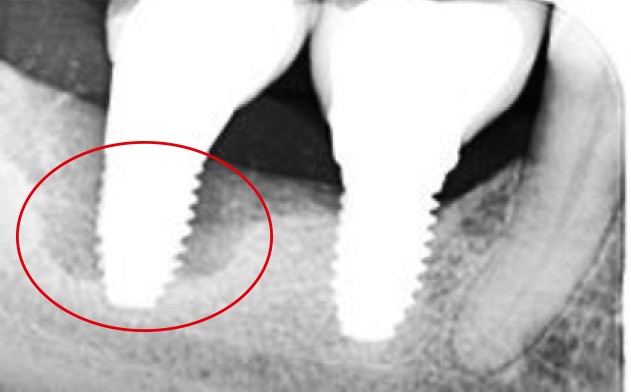

La péri-implantite

La plaque bactérienne (biofilm) pénètre et envahit les tissus muqueux autour des implants dentaires (fig. 3). S’installent une inflammation de la muqueuse péri-implantaire et la perte progressive et asynchrone du tissu osseux [4]. La péri-implantite survient au cours des premières années de mise en fonction de l’implant [4] et en l’absence de traitement, la maladie progresse (fig. 4) de manière non linéaire et rapide [4, 7].